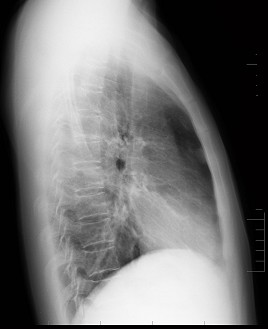

男性患者,38岁,突感胸部不适,X线检查如图,最可能的诊断是 ( ) 1JZ-03951.jpg 1JZ-03952.jpg

• A.肺部炎症

• B.胸腔积液

• C.肺结核

• D.正常心、肺、膈

• E.气胸